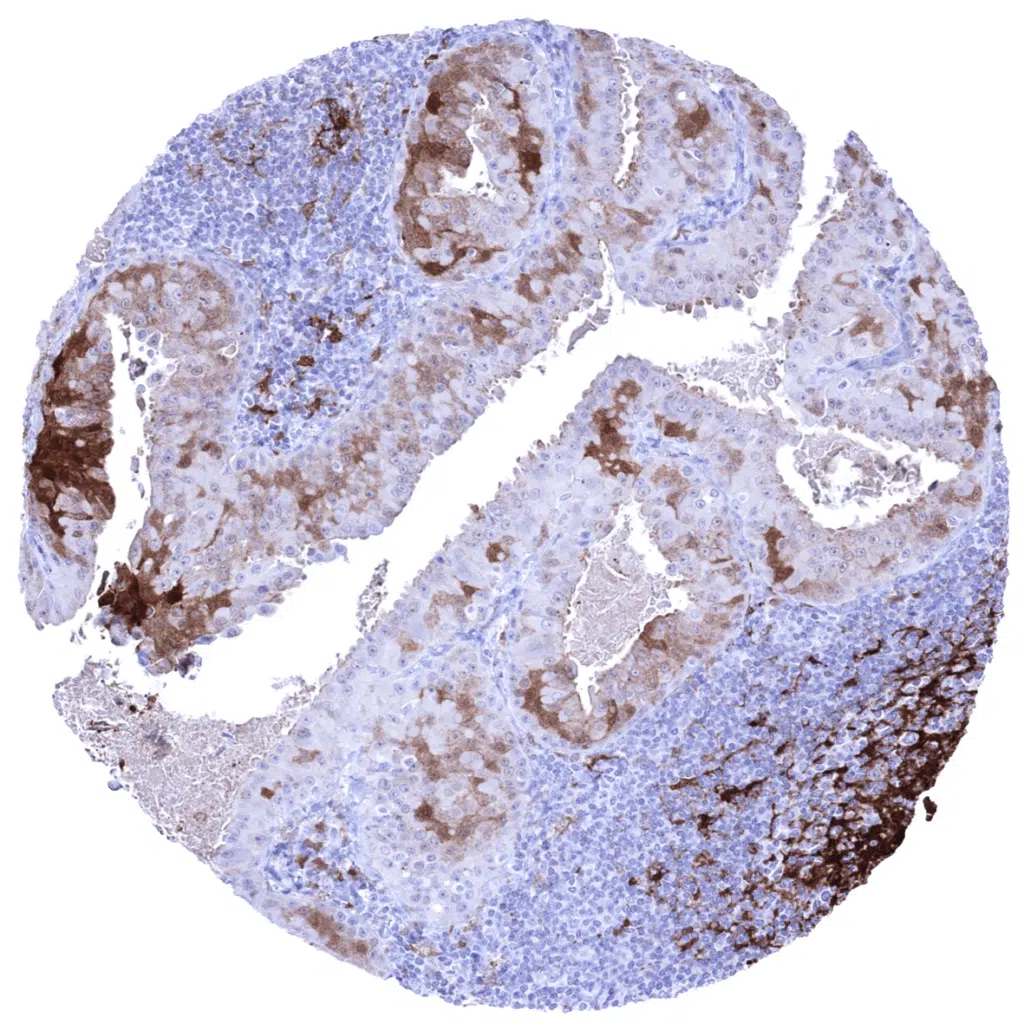

Lymph node- Cystatin A negative follicular B-cell lymphoma showing abundant Cystatin A expression in dendritic cells.